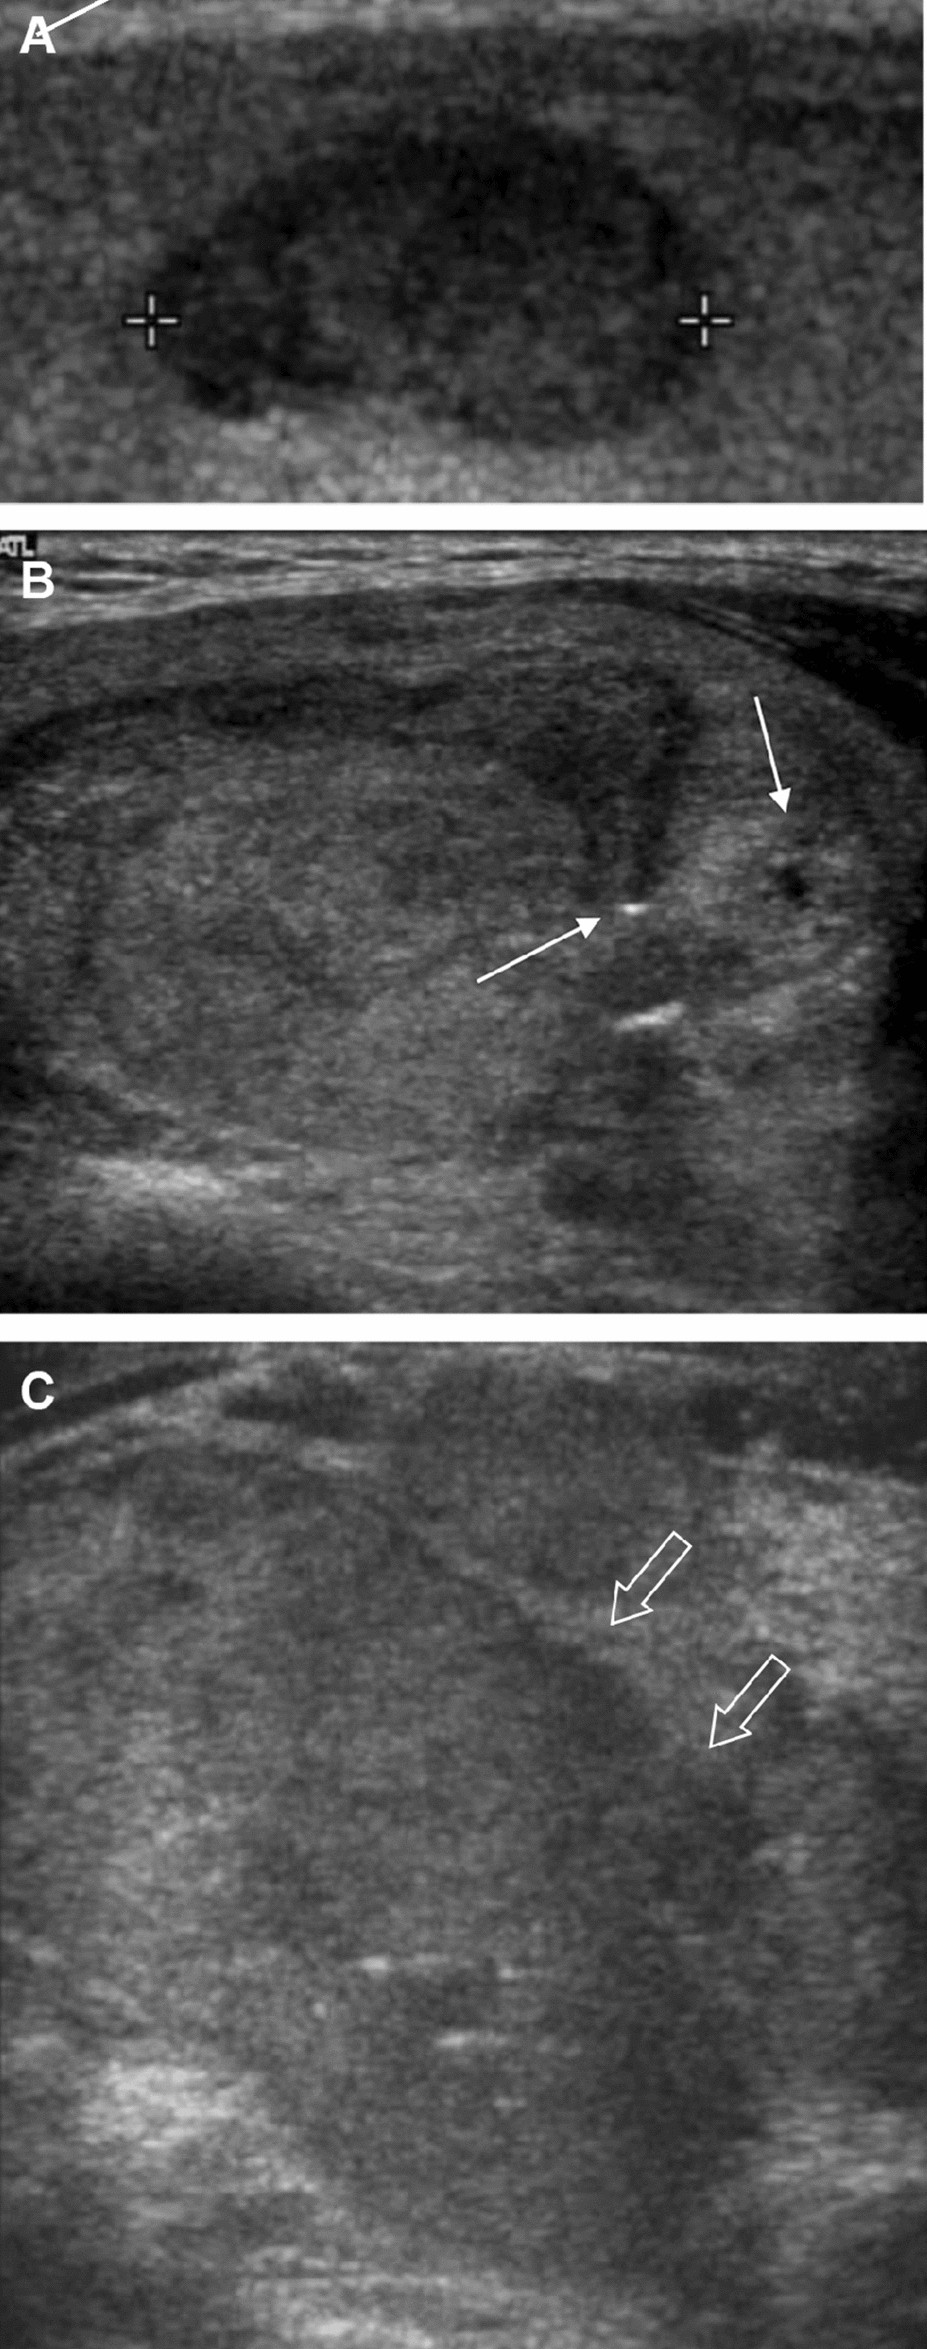

Figure 2

The TERT promoter mutated follicular thyroid carcinomas. Transverse ultrasound images show solid hypoechoic nodules with markedly decreased echogenicity (A), punctate echogenic foci (solid arrow) (B), or irregular margins (open arrow) (C). They were categorized as K-TIRADS/ACR-TIRADS category 4 (A and B), and K-TIRADS/ACR-TIRADS category 5 (C).